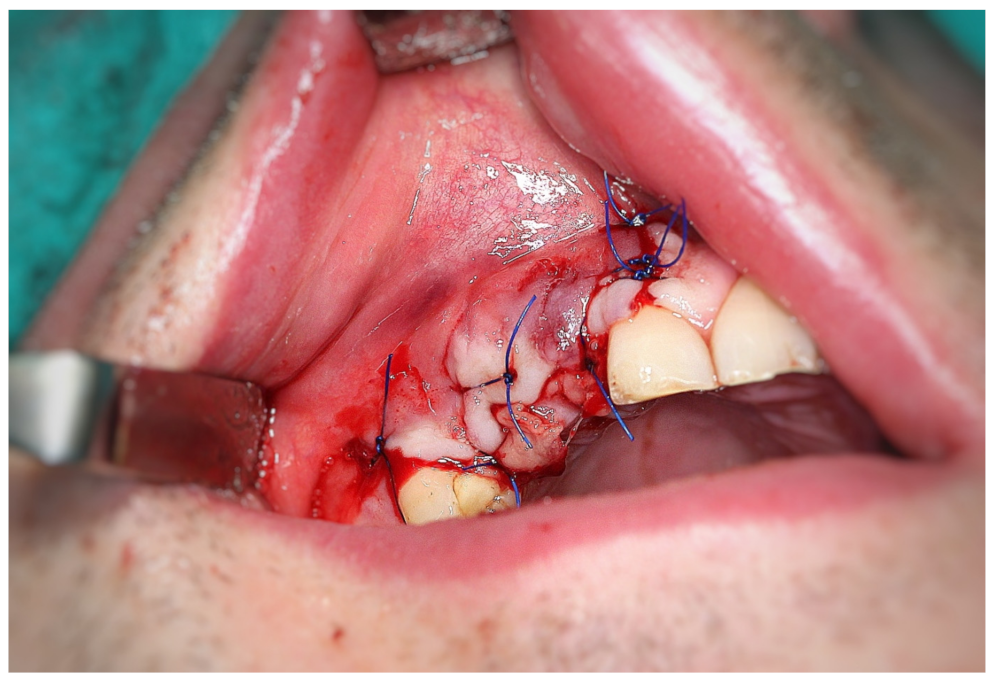

3.2. Surgery